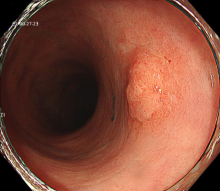

图示:食管早癌在内镜下NBI观察呈片状褐色改变,ME-NBI观察,微血管扭曲、紊乱